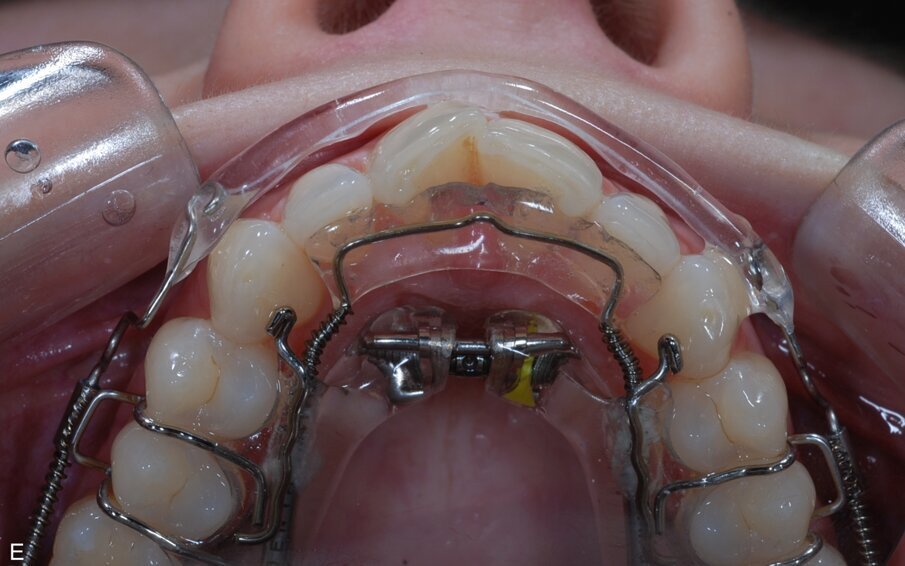

Fig. 9: ClearSmile Inman Aligner fitted

At the initial appointment, palatal anchors were placed, with interproximal reduction (IPR) and predictive proximal reduction (PPR) carried out using the guide issued from the laboratory. The patient was instructed on how to turn the expander. Aligner in situ. At the initial appointment, palatal anchors were placed, with interproximal reduction (IPR) and predictive proximal reduction (PPR) carried out using the guide issued from the laboratory. The patient was instructed on how to turn the expander. Aligner in situ. |

Progress with crowding on target at this point thanks to use of expander. IPR strips used and space between UR1 and UL1 polished. Progress with crowding on target at this point thanks to use of expander. IPR strips used and space between UR1 and UL1 polished. |

Patient had turned the expander eight times by this point – instructed to stop. PPR carried out on Patient had turned the expander eight times by this point – instructed to stop. PPR carried out on the central incisors, with space between UR1 and UL1 polished again. Discs used distally on the canines, with a composite anchor placed on UR1 and composite anchor removed from UL1. |